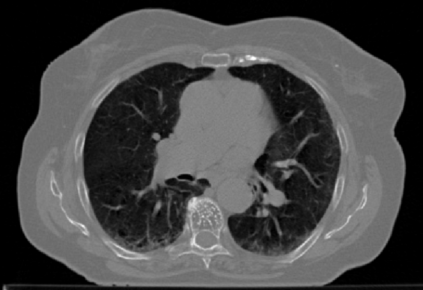

The COVID-19 pandemic has had a considerable impact on day-to-day life. Tackling the disease by providing the necessary resources to the affected is of paramount importance. However, estimation of the required resources is not a trivial task given the number of factors which determine the requirement. This issue can be addressed by predicting the probability that an infected patient requires Intensive Care Unit (ICU) support and the importance of each of the factors that influence it. Moreover, to assist the doctors in determining the patients at high risk of fatality, the probability of death is also calculated. For determining both the patient outcomes (ICU admission and death), a novel methodology is proposed by combining multi-modal features, extracted from Computed Tomography (CT) scans and Electronic Health Record (EHR) data. Deep learning models are leveraged to extract quantitative features from CT scans. These features combined with those directly read from the EHR database are fed into machine learning models to eventually output the probabilities of patient outcomes. This work demonstrates both the ability to apply a broad set of deep learning methods for general quantification of Chest CT scans and the ability to link these quantitative metrics to patient outcomes. The effectiveness of the proposed method is shown by testing it on an internally curated dataset, achieving a mean area under Receiver operating characteristic curve (AUC) of 0.77 on ICU admission prediction and a mean AUC of 0.73 on death prediction using the best performing classifiers.